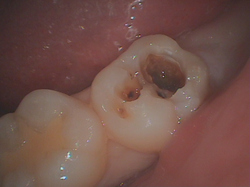

また入り口は小さいのですが、中で大きく広がっている事が多くあります。

入口は小さいのですが、削っていくと大きな穴になっていました。